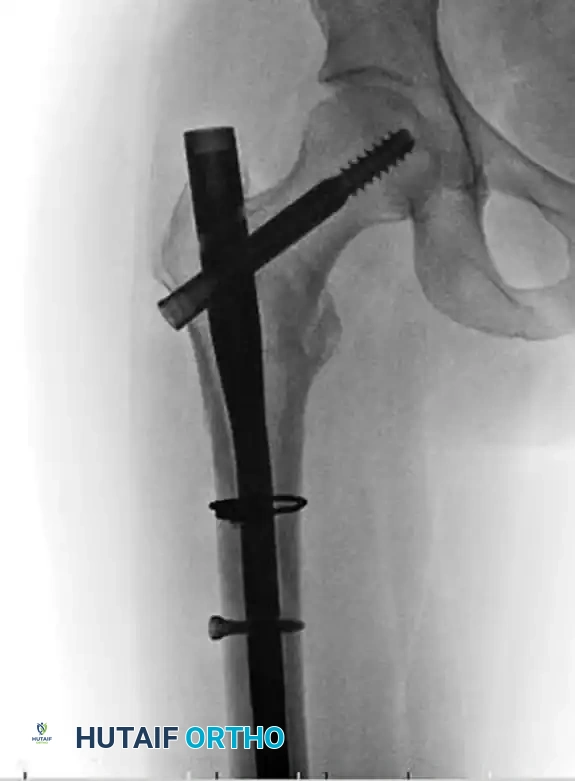

Figure E: Fluoroscopic confirmation of successful reduction prior to definitive plate application.

In cases where the reduction is highly unstable, a strategically placed cerclage wire can be utilized to hold the correction of the proximal segment deformity temporarily or definitively.

Figure F: Preoperative radiograph showing a long oblique subtrochanteric fracture highly susceptible to shear forces.

Figure G: Postoperative radiograph demonstrating the use of a cerclage wire to anatomically reduce and hold the proximal segment deformity, supplemented by a locking plate.